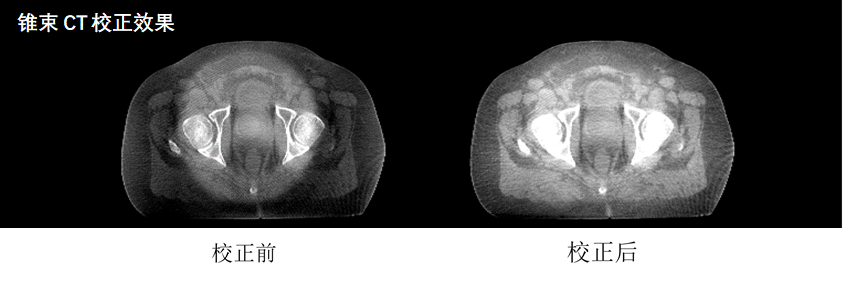

但是,锥束CT单次旋转成像体积大,光子散射严重并造成图像伪影,极大制约了成像质量。为了解决这个难题,杨益东团队提出了一种稳定可靠、准确快速的锥束CT图像重建算法。该方法利用患者诊断CT中的先验信息,通过局域滤波,准确地计算、消除锥束CT投影中的散射信号,从而实现对锥束CT图像的伪影校正。

经过校正后的图像,CT像素值误差减少了百分之九十(从大于150HU降到15HU以内),图像均匀度和对比度显著提升,放疗放射剂量计算的准确度及肿瘤病灶和软组织器官的辨识度均大幅改善。同时,该算法采用了GPU计算加速,整个锥束成像用时仅33秒,大幅提高了成像效率。该论文通讯作者是我院肿瘤放疗科杨益东教授,中国科学技术大学崔贺贺同学是论文第一作者。论文题目是“Planning CT Guided Robust and Fast Cone-beam CT Scatter Correction Using a Local Filtration Technique”。